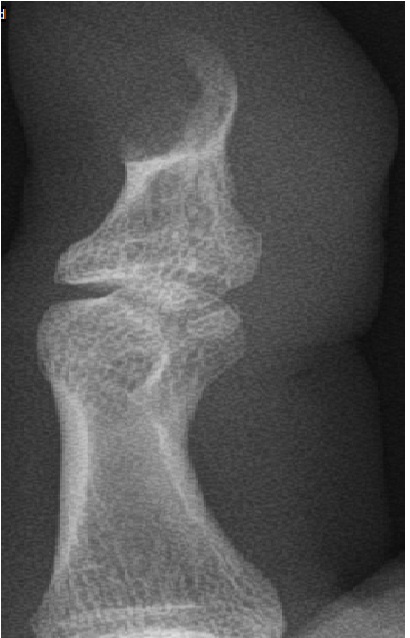

An Innovation in the Management of Osteolytic Lesions in Distal Phalanges of Digits